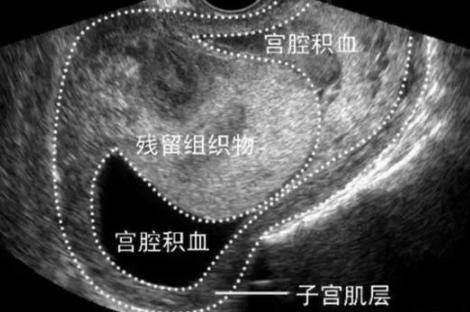

产后恶露不尽有什么表现?分娩4天后恶露仍然是鲜红色,且伴有臭味,引起发烧和寒战,严重的时候,还会晕倒。因此,产后恶露不尽,女性朋友一定要引起重视。...

生完孩子以后子宫会有一个自我修复的过程,在这个过程中就会拍出子宫内以及产道的分泌物等等,形成产后恶露。产后恶露一般一个月左右就干净了,每位产妇都应该注意观察自己的...

产后恶露是怎么形成的。我们都知道产后是会有恶露的,恶露一般会在三周左右排干净,那么关于恶露到底是什么,相信很多人都不是很了解吧。我们就来说一说恶露吧。...